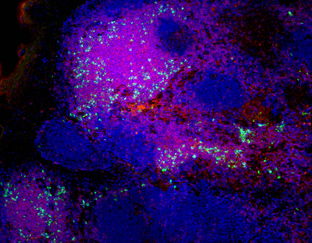

Illuminating tumour micro environments

Advanced technical imaging capabilities and research projects supported by MWC are helping to identify new prognostic and diagnostic biomarkers to advance potential therapeutic tar

New imaging improves our understanding of the immune system

Maurice Wilkins Centre researchers have used novel imaging technology to reveal the structure and inner workings of entire lymph nodes, core components of the body’s immune system.

Mapping microscopic worlds

Maurice Wilkins Centre researchers have used unique microscopic imaging techniques to peer into the three-dimensional structure of blood vessel networks – and new computational tec

Exquisite networks (2011)

Innovative technology developed to study the heart has been adapted for a unique study of the immune system – and will now be applied to cancer, through cross-disciplinary links fo

Lighting up lymph nodes (2009)

Maurice Wilkins Centre researchers have made exciting new discoveries about how human lymph nodes work.